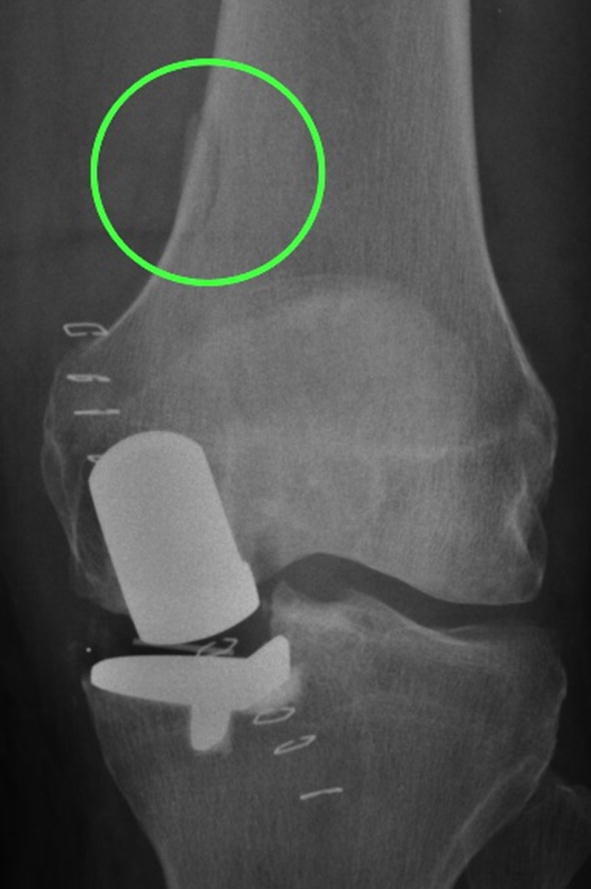

Fig. 3.

A post-primary and pre-revision radiograph of a poorly positioned tibial component leading to tibial loosening

Fig. 4.

A medial tibial cut leading to tibial component undersizing and posterior underhang. The posterior tibial tray subsequently subsided into the cancellous bone

Fig. 5.

A post-primary anteroposterior radiograph demonstrating a malaligned femoral component, which is likely due to a malpositioned intramedullary guide rod that has pierced the femoral cortex (circled)

Although surgical errors were noted in 62% of the operations, only 6% were considered to be major, meaning they would cause symptoms and require a revision. The remainder were considered minor implying they probably would not compromise the outcome. However, if for some unrelated reason, the patients had symptoms, surgeons unfamiliar with the device might do a revision believing a minor surgical error was responsible for the symptoms. The majority of errors were with tibial cut height and tibial component orientation, which commonly occurred with the instrumentation (Phase 3) used at that time. New instrumentation (Microplasty) is now used and includes a stylus with slotted saw guides to control cut height and orientation, and a system that links the femoral drill guide to an intramedullary rod to improve femoral component orientation [18, 23, 36]. Cementation errors were also noted frequently, and the introduction of cementless components should prevent these. Undersized tibial components are at risk of subsidence, and the majority of these were associated with a vertical cut that was too far medial (Fig. 4). The vertical cut should be just medial to the apex of the medial spine.